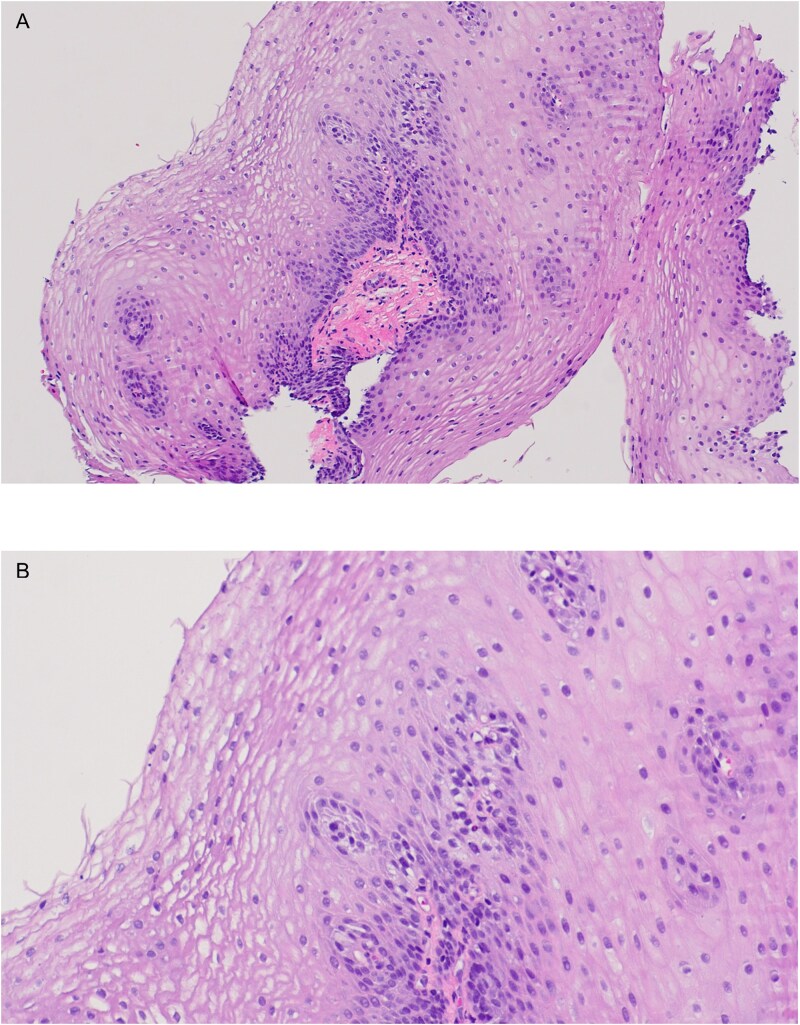

Eosinophilic Esophagitis (EoE) is a chronic, immune-mediated disorder characterized by eosinophilic infiltration of the esophageal mucosa. EoE presents a clinical challenge as the underlying esophageal dysfunction results in diverse symptomatology, ranging from feeding difficulties and failure to thrive in infants to dysphagia and food impaction in older children. The treatment and long-term management of EoE involves a multidisciplinary approach that may include topical glucocorticosteroids, diet therapy and other evolving pharmacotherapies. We present a case of a 12-month-old previously healthy female with a 3-week history of illness followed by an acute presentation of feeding intolerance and hypersensitivity reactions who was subsequently diagnosed with EoE.